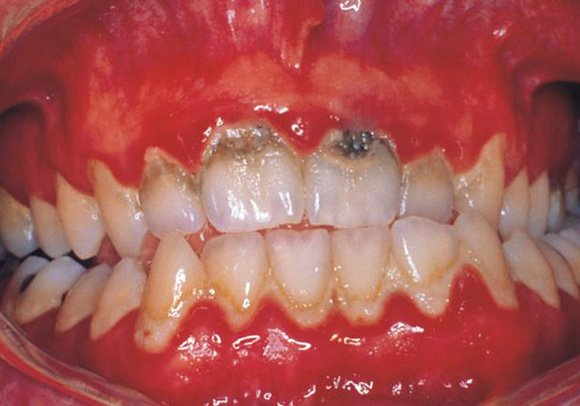

При диагностике стоматологических заболеваний врачи ориентируются на симптомы, указывающие на некроз твердых тканей зуба:

- повышенная чувствительность к горячим и холодным продуктам;

- неожиданная оскомина, не связанная с кислой пищей;

- снижение блеска эмали, ее бледность и тусклость;

- образование белых меловых пятен, которые могут потемнеть;

- неоднородный цвет пигментных образований: темный центр и светлые края;

- шероховатость и неоднородная структура пораженных участков;

- отслаивание эмали при использовании зонда;

- постоянные ноющие боли у некоторых пациентов;

- быстрое разрушение режущего края зуба, ухудшающее жевательную функцию и приводящее к стиранию поверхности и нарушению прикуса;

- уменьшение размера зубов и приближение краев к десне в запущенных случаях.

Изменения цвета зуба зависят от воздействия различных факторов. Например, соляная кислота придает эмали желто-серый оттенок, а серная – черный. Высокая концентрация азотистых веществ может вызвать меловые пятна и разрушение структуры.

- Пришеечный – как очевидно из названия, он поражает пришеечный участок эмали, ближе к десне, а иногда и уходит под нее. Начинается все с малозаметного белого пятна, похожего на мел. Но заболевание быстро прогрессирует и пораженная область темнеет, становясь коричневым или даже черным. Патогенное образование активно разрастается, охватывая все большие объемы и рядом стоящие единицы. При воздействии стоматологическими инструментами поверхность эмали легко соскабливается, расслаиваясь в пораженных участках. Пациент жалуется на повышенную чувствительность при употреблении горячей или холодной пищи.